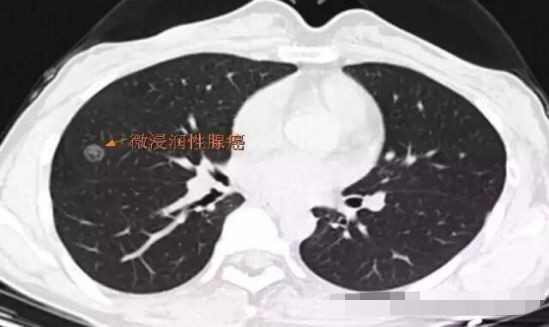

病例3

突然出现的磨玻璃结节